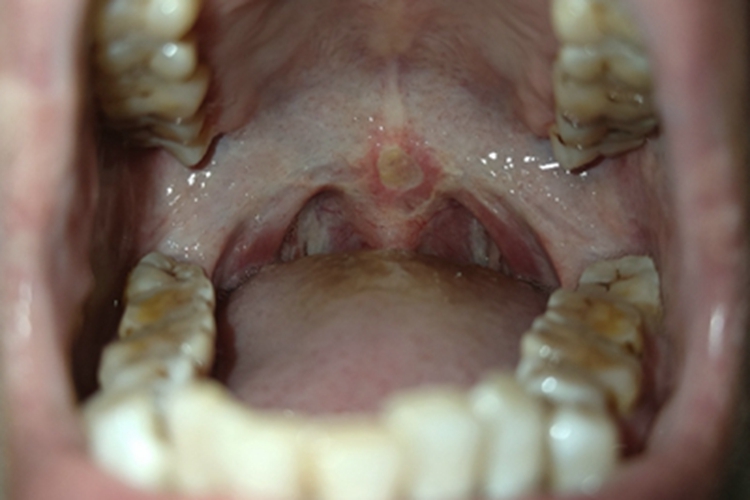

口腔溃疡可发生于软腭处,可表现为溃疡表面覆盖一层黄白色假膜。

口腔溃疡的损害可发生于软腭处,临床上可表现为溃疡表面覆盖一层黄白色假膜,中央凹陷,边界清楚,周围黏膜红肿,患者可感吞咽时疼痛明显。